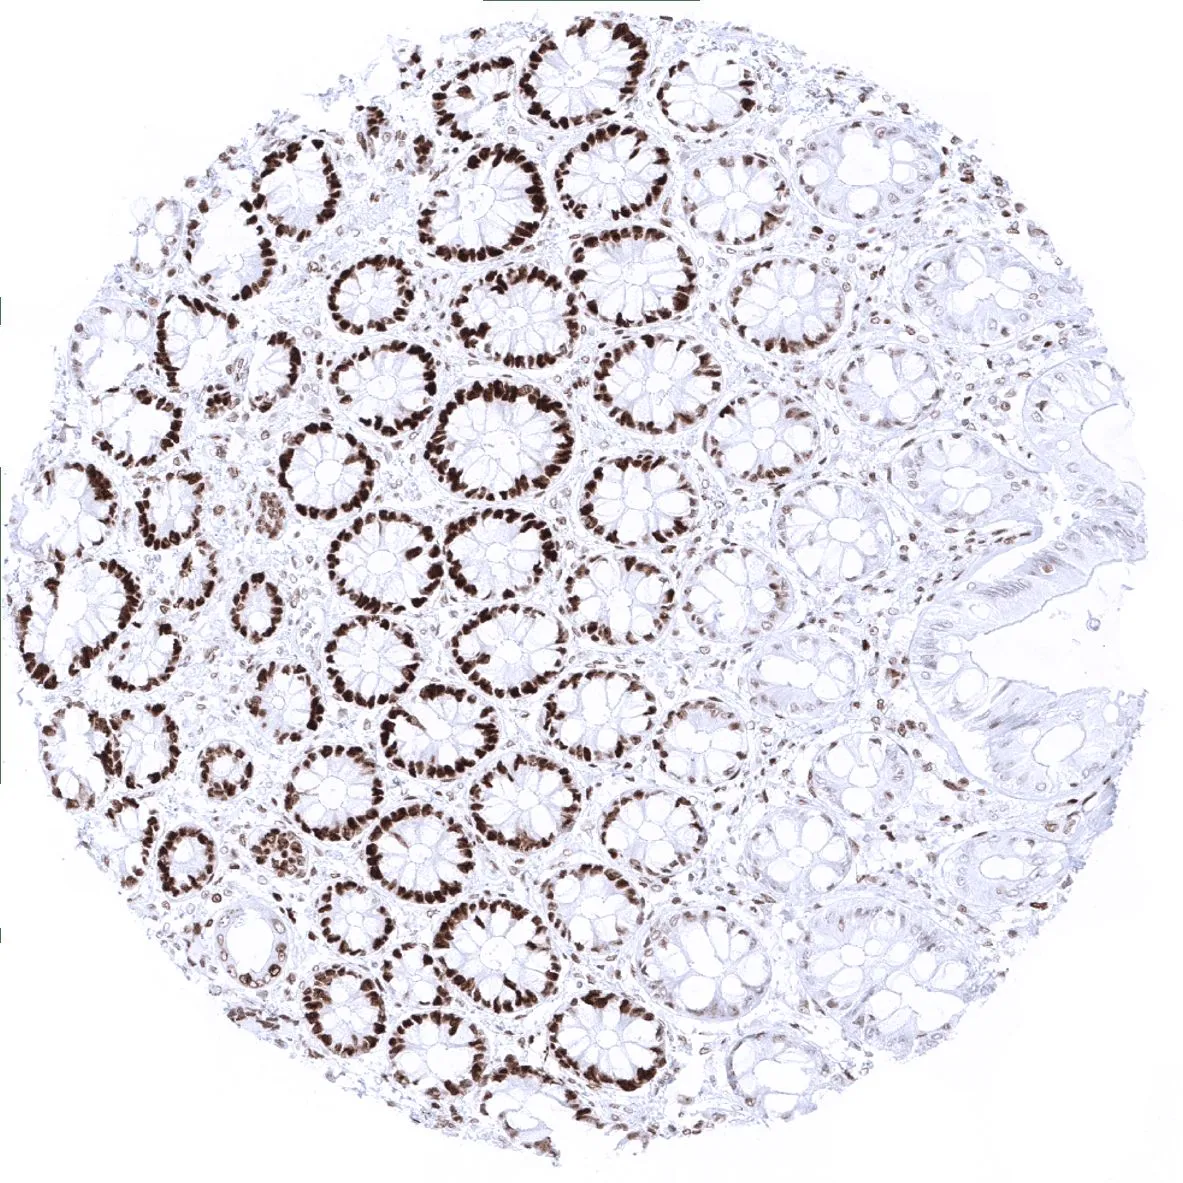

IHC-P analysis of human mucosa from descending colon tissue using GTX04416 MSH6 antibody [MSVA-906R] HistoMAX™.